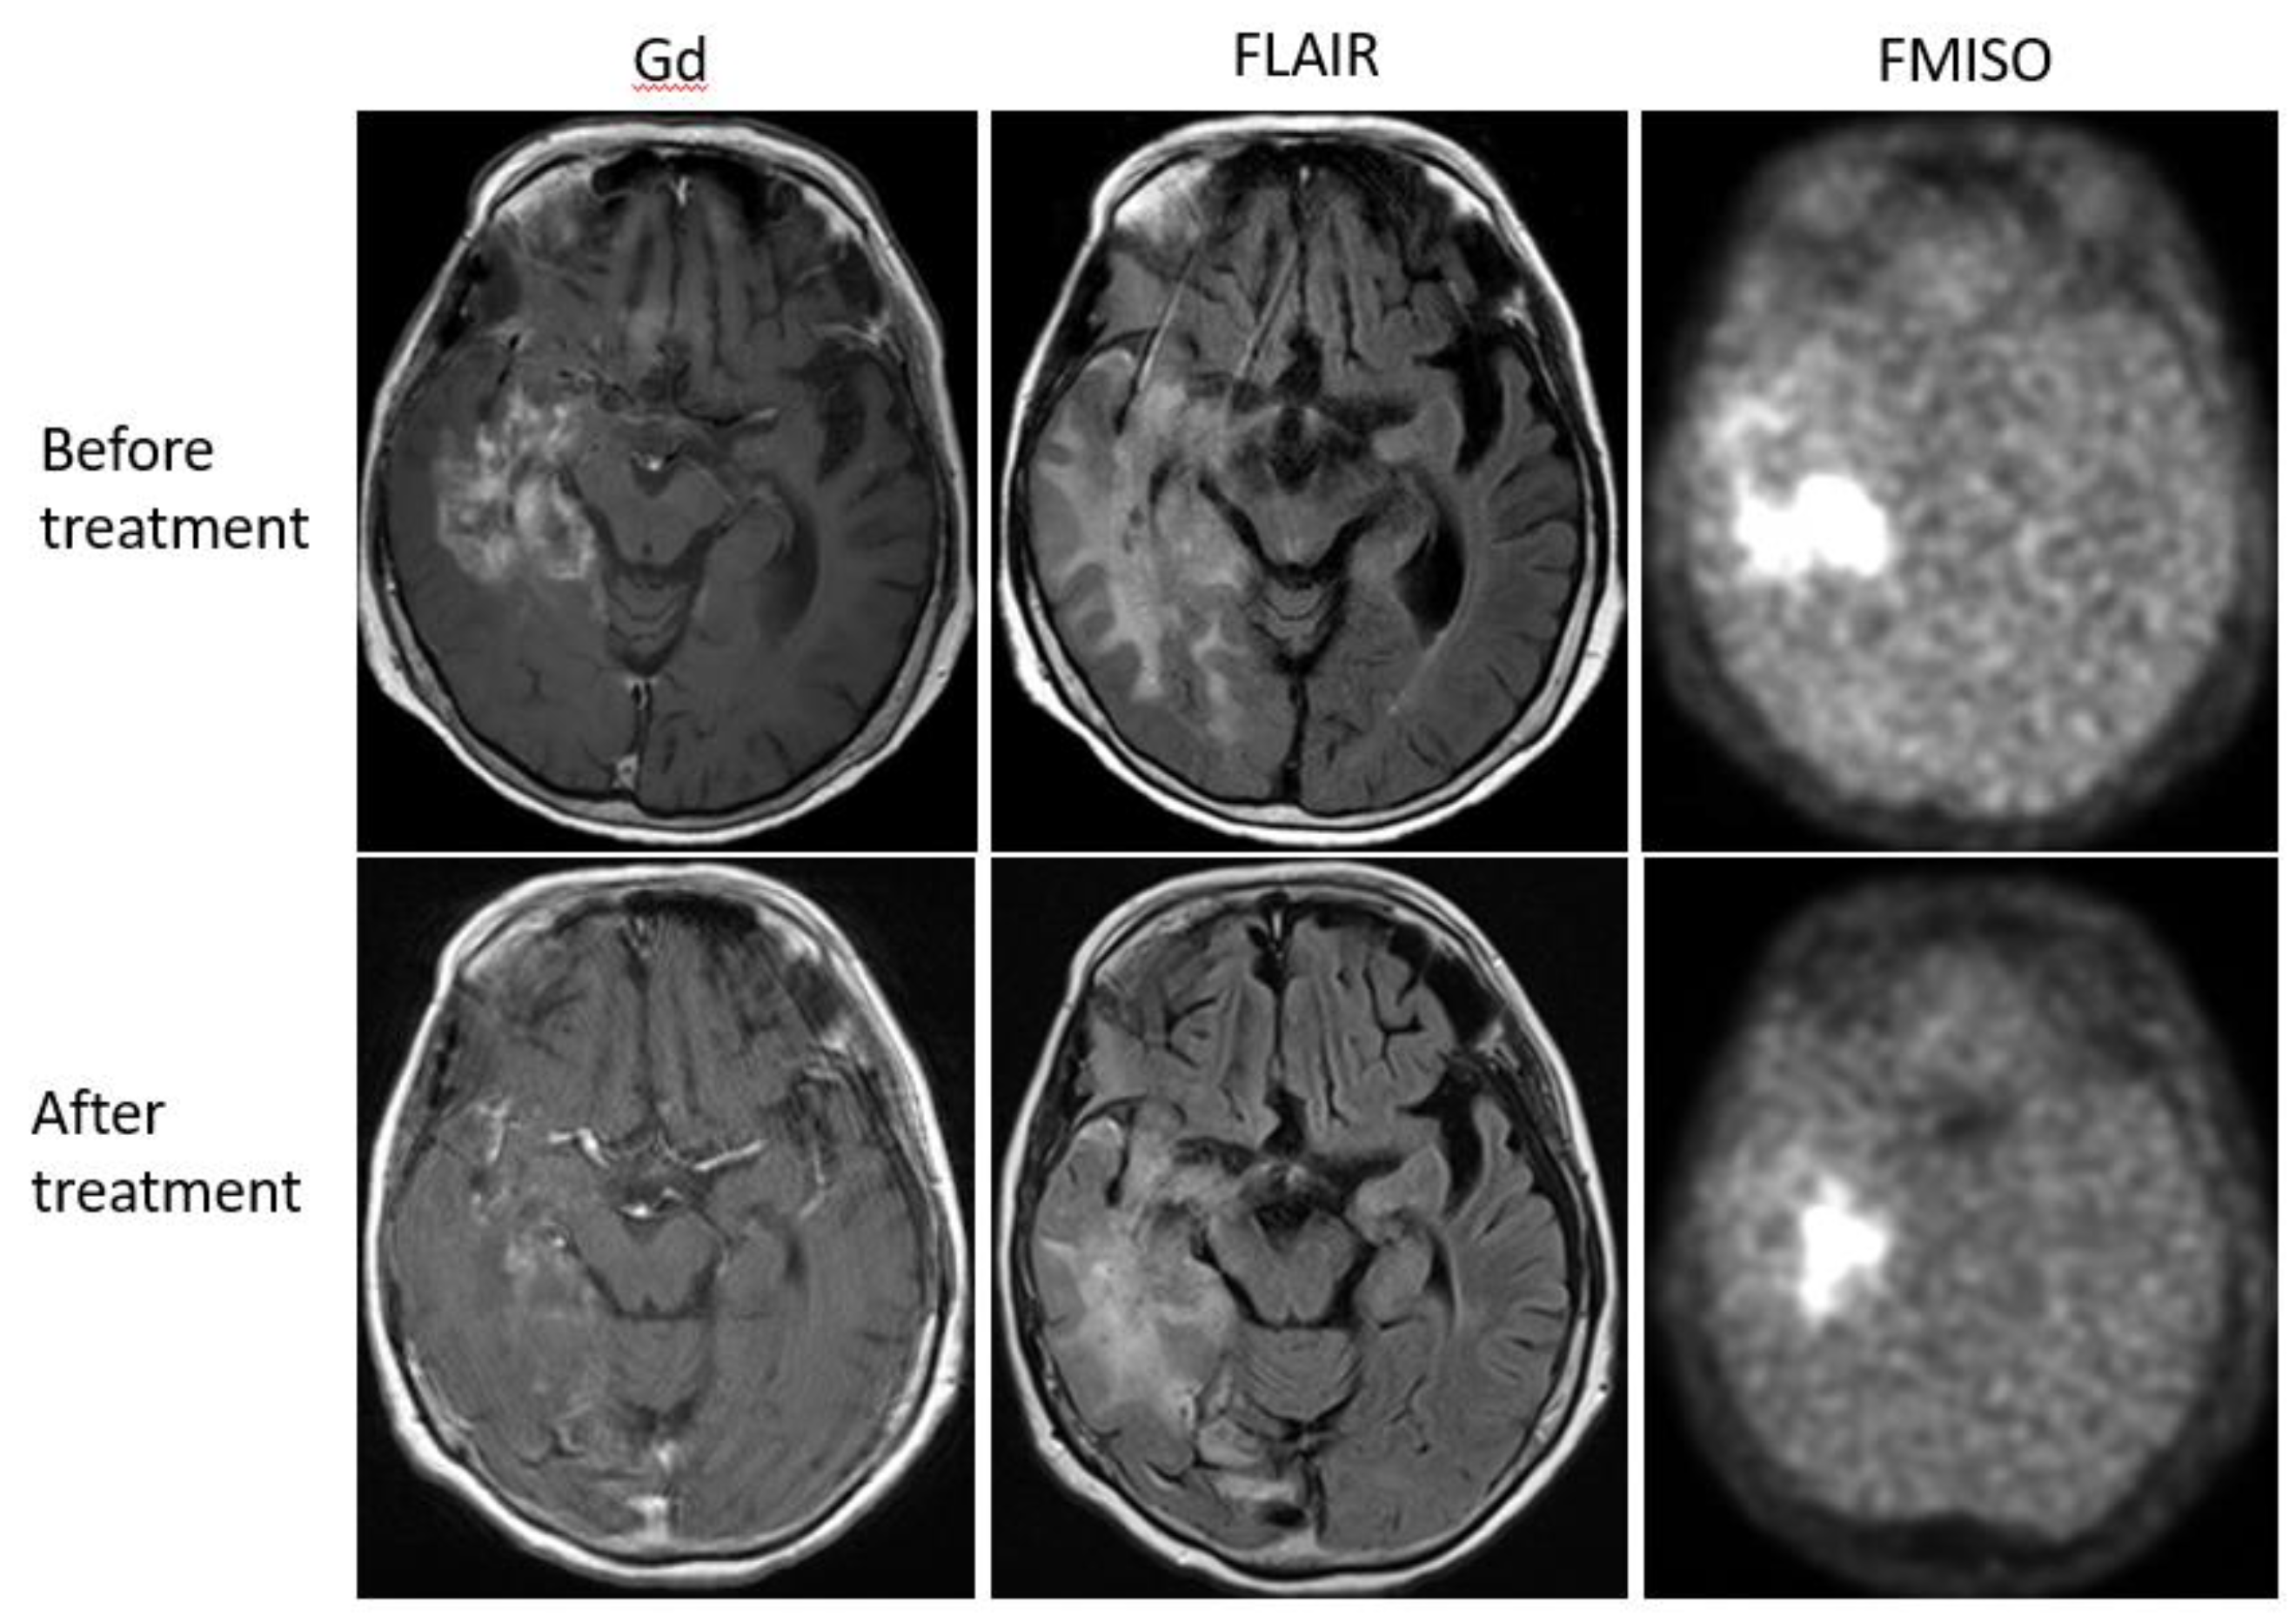

Bevacizumab is a recombinant humanized monoclonal antibody that blocks angiogenesis by inhibiting vascular endothelial growth factor A (VEGF-A) [58]. Although bevacizumab failed to prolong the overall survival of patients with primary glioblastoma [59,60], it was effective in some populations of recurrent glioma patients. In our retrospective study, we investigated whether FMISO PET has the potential to distinguish responders to bevacizumab from non-responders [61]. Eighteen patients with recurrent glioma underwent bevacizumab treatment. We compared the patients’ pre-and post-MRI and FMISO PET to classify them as (1) MRI-FMISO double responders (n = 9, Figure 5), (2) MRI-only responders (n = 5, Figure 6), and (3) non-responders (n = 4, Figure 7). There were no FMISO-only responders. The survival analysis demonstrated that the MRI-FMISO double responders had significantly longer overall survival than the other patients, whereas no significant difference was observed between the MRI-only responders and the non-responders. We thus concluded that recurrent gliomas with decreasing FMISO accumulation after short-term bevacizumab application could derive a survival benefit from the treatment.

Figure 6. A 68-year-old patient with anaplastic astrocytoma showed a strong uptake of FMISO before the bevacizumab treatment (upper row). After the treatment, MRI showed shrinkage of the tumor, but FMISO uptake was still observed (lower row). The patient was considered a ‘MRI-only responder’.

Figure 7. A 36-year-old patient with glioblastoma showed no FMISO uptake before the bevacizumab treatment (upper row). After the treatment, the patient presented with the enlarged tumor in the bilateral frontal lobe (lower row). The tumor showed high FMISO uptake. This patient was considered a ‘non-responder’.